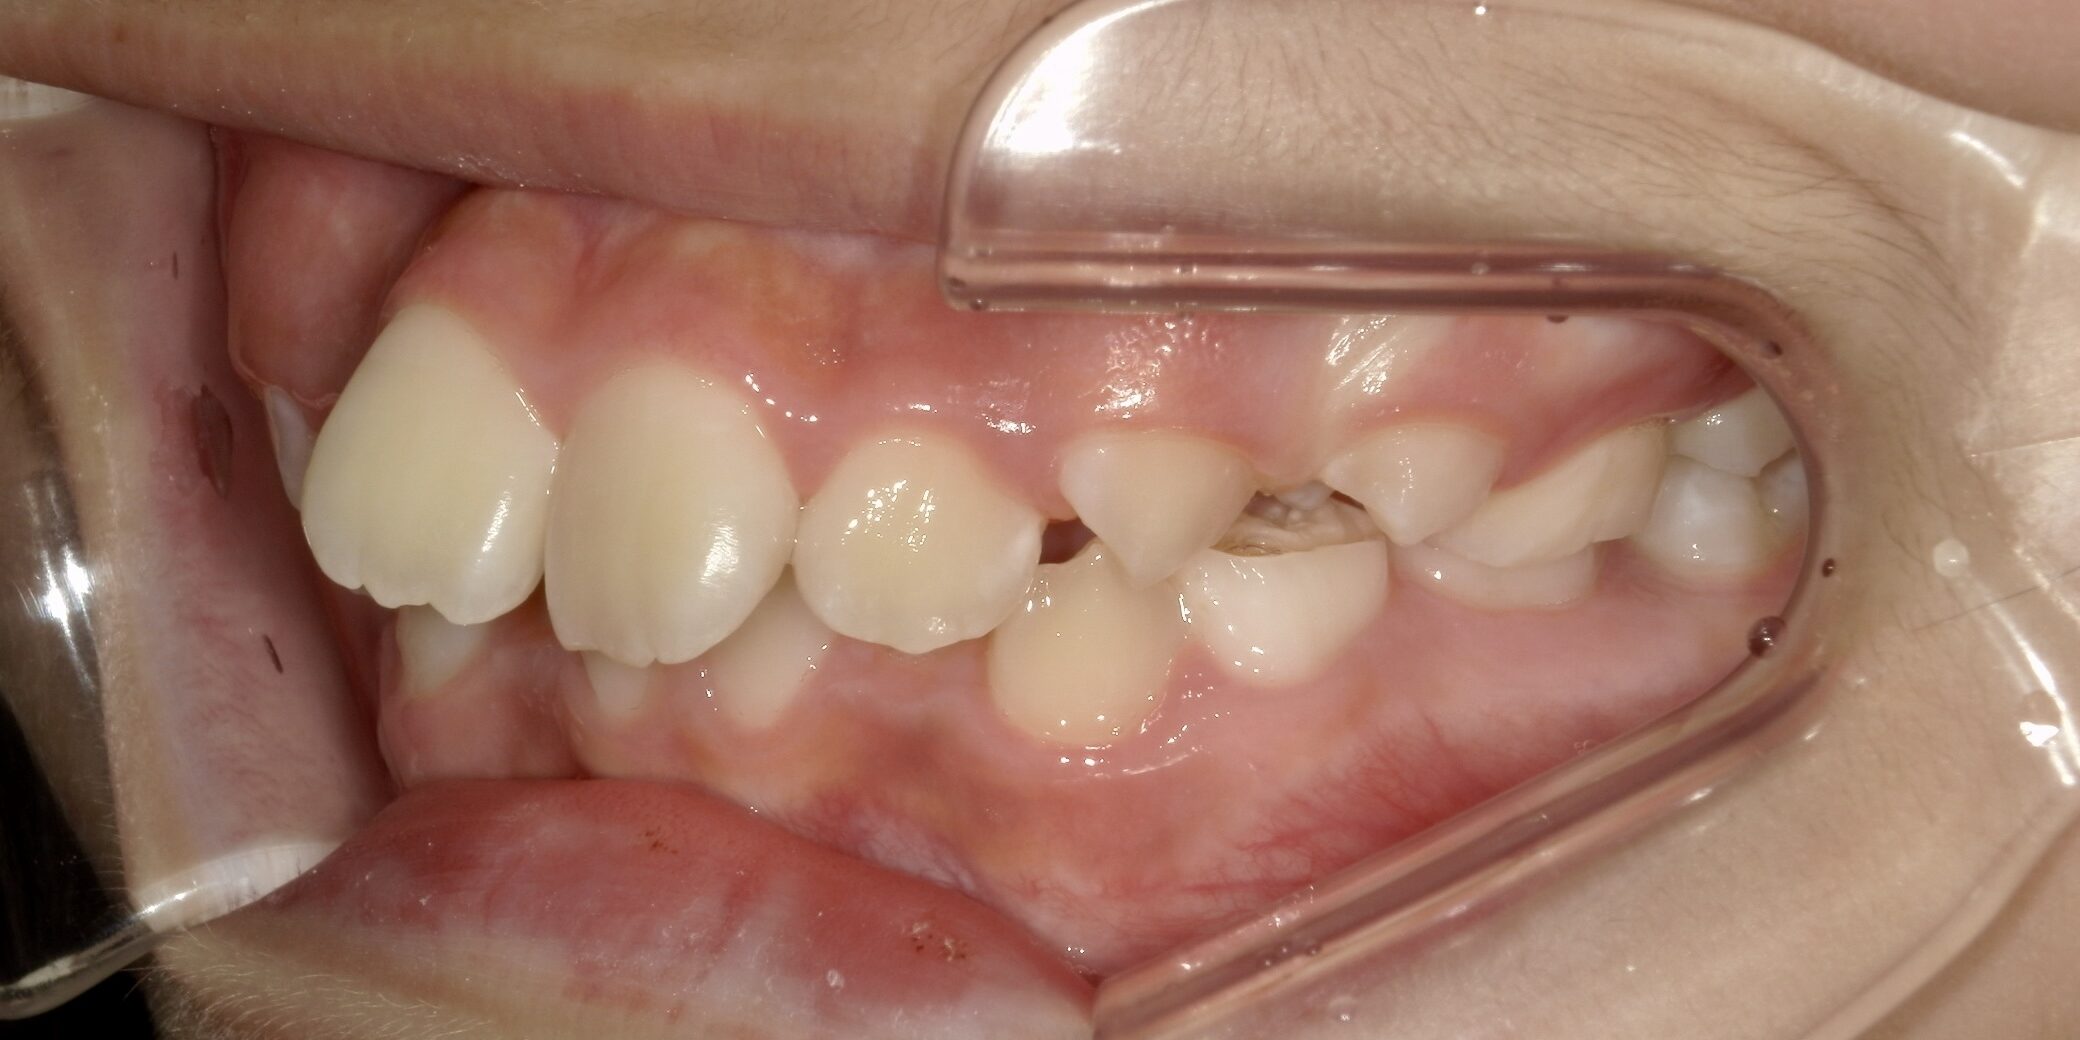

治療前/横から見た歯並び

出っ歯傾向が強く見られます。 また噛み合わせが深く、下の前歯が見えません。 -